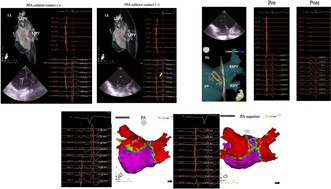

心房P波后的正偏转在单极电图中可作为脉冲场消融过程中导管与组织接触的实用替代标记;与不同解剖区域的有效病变形成相关。

A positive deflection following the atrial P wave in unipolar electrograms serves as a practical surrogate marker for catheter-tissue contact during pulsed field ablation; correlating with effective lesion formation across diverse anatomical regions.